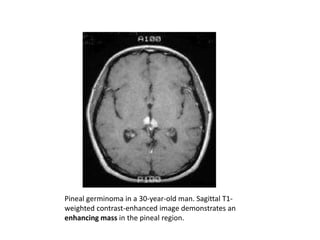

MASS IN THE PINEAL REGION.

Pineal germinoma in a 30-year-old man. Sagittal T1-

weighted contrast-enhanced image demonstrates an

enhancing mass in the pineal region.